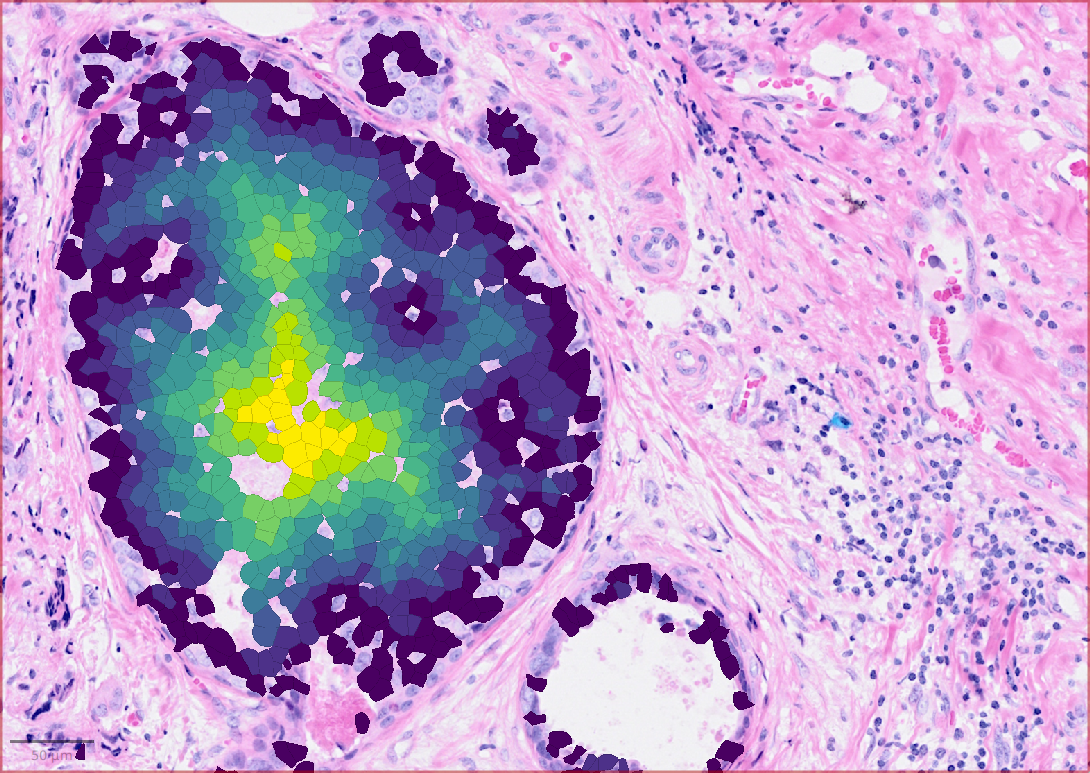

Refer to caption

(a) Neighboring cell connectivity

(b) Distance to the boundary of a specific cell-type cluster

(c) Cell-cell interaction: MMP2->PECAM1

(d) DBSCAN-CellX based cell clustering

Figure 2: Results showing some functions provided by QuST: (a) Neighboring cell connectivity based on Delaunay clustering. Various single cell analyses available in QuST are based on the neighboring cell connectivity. (b) QuST’s cellular spatial profiling generates a heat map indicating the distance to boundary of a specific cell type, e.g., tumor epithelial cells to the corresponding tumor boundary. (c) The heat map showing the cell-cell interaction intensity of the given LR pair, e.g., MMP2->PECAM1. (d) Result of QuST’s DBSCAN-CellX implementation.

The results showing in Figure 2 represents some comprehensive analyses of the experimental data using a range of powerful functions provided by QuST. First, given the fact that many spatial biological analyses rely on cellular spatial analysis, the Delaunay clustering method implemented in QuPath is employed to generate neighboring cell connections. For example, QuST’s cellular spatial profiling, which generates a heat map that indicates the boundary distance of individual cells, e.g., the distance from a cancer epithelial cell to the boundary of the corresponding tumor boundary. Based on the heat map, one can explore the differential gene expression patterns between the intratumoral tumor cells and the tumor cells present in the immune-invasive region, which are located on the surface of the tumor. Next, QuST’s LR-product method offers an additional layer of analysis by generating a heat map that illustrates the intensity of cell-cell interaction for a specific LR pair. This heat map provides a quantitative measure of the strength and significance of communication between specific pairs of cells. Finally, a result of QuST’s DBSCAN-CellX implementation is shown, which provides a comprehensive understanding of spatial relationship of the chosen cell clusters.